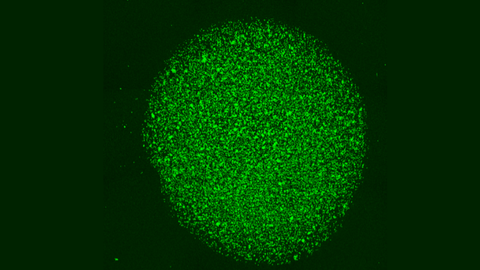

Por iso, un proxecto con investigadores do CSIC está a estudar o desenvolvemento de cápsulas biolóxicas nas que se albergarán estas células CAR-T coas que tratar de forma específica este tipo de tumores sólidos. Nel participan o Centro de Investigación contra o Cancro de Salamanca (CIC, un instituto mixto de investigación do CSIC e a Universidade de Salamanca), o Centro de Investigación Biomédica en Rede de Cancro (CIBERONC), a Universidade de Santiago de Compostela (USC), o Centro de Fabricación de Terapias Avanzadas de Galicia (GALARIA), e o CIMA Universidade de Navarra.

José Rivas Rey, coordinador do proxecto e catedrático do Departamento de Física Aplicada da Universidade de Santiago de Compostela, confesa que o principal reto deste proxecto, que finaliza este ano, foi «que esas células CAR-T liberásense e mantivesen vivas e activas na cápsula durante tempos prolongados». Para entendelo mellor, detalla que, primeiro, elaboraron as cápsulas cun polímero natural que «funciona como un colector de dous ou tres milímetros dentro das cales van embebidas as células CAR-T cun cóctel de moléculas bioactivas que as mantén vivas e activas». As células multiplícanse dentro das cápsulas e «poden saír durante máis de vinte días, o que permite o seu uso localizado dentro do tumor durante tempos prolongados».

A boa noticia, remarca Rivas, é que os resultados son positivos. «Fixemos un estudo in vivo, con resultados moi positivos. Estamos moi contentos porque os tumores se reduciron, necesitándose para iso números de células CAR-T moi inferiores a cando estas se administran no torrente circulatorio como é habitual». Aínda que, opta pola prudencia: «Que funcione neste ámbito, ata chegar á clínica, falta un gran paso». Do mesmo xeito que Troia non se conquistou nun ano, estas biocápsulas con células CAR-T tamén necesitan tempo para acabar cos tumores sólidos. «En dous ou tres meses remataremos este proxecto no que levamos tres anos e os resultados son prometedores, pero aínda quedan moitos controis e maduración», comenta Rivas.

Xosé Bustelo tamén é un dos investigadores principais deste proxecto. «Creo que o interesante deste desenvolvemento, que ata o de agora é soamente preclínico, é permitirnos levar directamente as células CAR-T de forma activa ao tumor sólido sen que estas se dispersen por todo o organismo, senón que xustamente queden alí onde son necesarias para a súa función. Co cal, temos máis soldados no campo de batalla que se utilizamos CAR-T "normais". Outro punto importante é que ese «biocóctel» que se atopa nestas cápsulas ten un ámbito de acción local, «o que evita efectos secundarios negativos como é a indución de reaccións inflamatorias a nivel de organismo», conclúe.